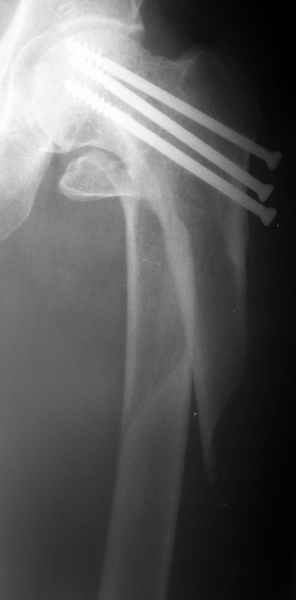

1LateralAnother lateral

Женшина 69 лет оперирована у нас 2 года назад по поводу перелома шейки. Ходила дома без дополнительной опоры, на улице - с тростью.Сегодня утром села мимо табуретки. Поскольку наша бывшая пациентка, сегодня же из области родственники привезли к нам. Картинка в приложении. Какие будут предложения по тактике?

Regarding this specific patient, it is quite difficult for me to discern the exact fracture pattern and therefore treatment suggestions. It appears to be a spiral fracture starting just proximal to the less trochanter and extending distally 6 or more cm into the shaft with medial displacement of the distal fragment. The lesser troch is a seperate fragment. The 2 year old femoral neck fracture appears to have healed in good position I really can't tell where the fracture starts laterally, but presumably it's near the distal most screw.

I can't tell if there is further comminution of the shaft or the greater trochanter. I can barely see the fracture on the lateral radiograph. I'm not sure but I don't see AVN of the femoral head nor OA of the hip. Her overall bone quality appears normal for a 68 year old. I don't see any loosening of the screws but I can't tell for sure.